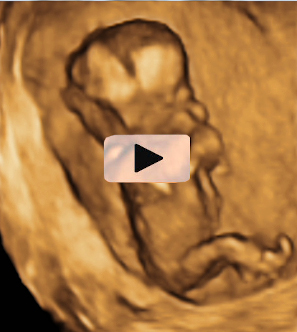

Ecografía Embarazo 4D Semana 12 - PRUEBAS DIAGNÓSTICAS